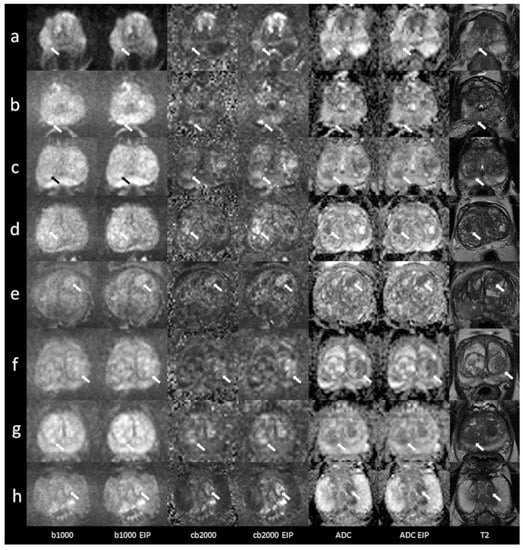

4.2.2. Peripheral Zone

4.2.3. Transition Zone